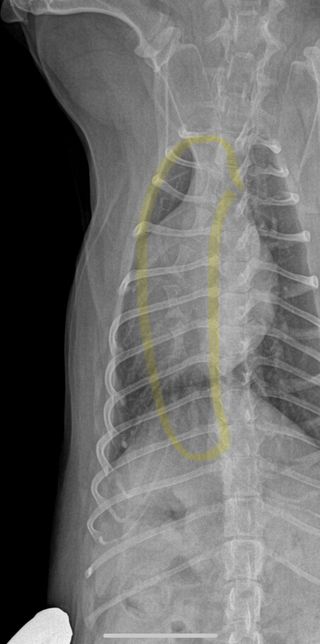

- 반려동물 건강반려동물Q. (이은수 수의사님) 하나만 더 여쭤보고싶습니다ㅠ 강아지 엑스레이 관련안녕하세요 강아지 건강검진 받고 엑스레이상 흉골이 휘었다고 했었는데요, 외부충격은 없고, 1년 전 다른 병원에서 찍은 엑스레이는 흉골 휘지 않았습니다. 사진상으로 휘어보이는거라고 하셨는데 잘못찍혔다는 말씀이실까요? 건강검진 병원에서는 1년전 다른 병원에서 찍은 엑스레이는 흉골이 휘지 않아서 폐쪽 문제일수도 있으니 ct가능한 병원가서 정확하게 보는게 좋을거같다는데, 폐에 문제가 생기면 심장이 쏠리면서 흉골이 휠수도있나요..? 엑스레이는 흉골이 휜거같아 이상해서 세번정도 찍었다고 하네요. 사진 보면 노란색 표시 흉골이 휘어있고 심장도 쏠려있습니다…잘못찍었다고 흉골이 휘고 심장도 쏠릴 수 있나요?!?첫번째 사진이 1년전 다른병원에서 찍은 엑스레이고 2,3번째가 이번에 찍은 흉골 휜 엑스레이입니다.. 3,4번째 흉골 휜 엑스레이 같은 사진인데 휜 흉골부분 노란색으로 표시해뒀습니다. R, L사진 둘 다 다른방향에서 찍은거같은데, 둘 다 휘어있습니다. 폐쪽의 문제일수도 있을까요? 기침이나 식욕감퇴 등의 다른 증상은 없고 변 상태도 좋습니다.

- 반려동물 건강반려동물Q. 강아지 엑스레이 잘못찍으면 흉골 휘어보이게 나오는건가요안녕하세요 강아지 건강검진 받고 엑스레이상 흉골이 휘었다고 했었는데요, 외부충격은 없고, 1년 전 다른 병원에서 찍은 엑스레이는 흉골 휘지 않았습니다. 사진상으로 휘어보이는거라고 하셨는데 잘못찍혔다는 말씀이실까요? 건강검진 병원에서는 1년전 다른 병원에서 찍은 엑스레이는 흉골이 휘지 않아서 폐쪽 문제일수도 있으니 ct가능한 병원가서 정확하게 보는게 좋을거같다는데, 폐에 문제가 생기면 심장이 쏠리면서 흉골이 휠수도있나요..? 엑스레이는 흉골이 휜거같아 이상해서 세번정도 찍었다고 하네요. 사진 보면 노란색 표시 흉골이 휘어있고 심장도 쏠려있습니다…잘못찍었다고 흉골이 휘고 심장도 쏠릴 수 있나요?!?첫번째 사진이 1년전 다른병원에서 찍은 엑스레이고 2,3번째가 이번에 찍은 흉골 휜 엑스레이입니다.. 3,4번째 흉골 휜 엑스레이 같은 사진인데 휜 흉골부분 노란색으로 표시해뒀습니다. R, L사진 둘 다 다른방향에서 찍은거같은데, 둘 다 휘어있습니다. 폐쪽의 문제일수도 있을까요? 기침이나 식욕감퇴 등의 다른 증상은 없고 변 상태도 좋습니다.

- 반려동물 건강반려동물Q. 강아지 엑스레이 흉골이 휘었다는데오안녕하세요 강아지 건강검진 받고 엑스레이상 흉골이 휘었다고 했었는데요, 외부충격은 없고, 1년 전 다른 병원에서 찍은 엑스레이는 흉골 휘지 않았습니다. 사진상으로 휘어보이는거라고 하셨는데 잘못찍혔다는 말씀이실까요? 건강검진 병원에서는 1년전 다른 병원에서 찍은 엑스레이는 흉골이 휘지 않아서 폐쪽 문제일수도 있으니 ct가능한 병원가서 정확하게 보는게 좋을거같다는데, 폐에 문제가 생기면 심장이 쏠리면서 흉골이 휠수도있나요..? 엑스레이는 흉골이 휜거같아 이상해서 세번정도 찍었다고 하네요. 사진 보면 노란색 표시 흉골이 휘어있고 심장도 쏠려있습니다…잘못찍었다고 흉골이 휘고 심장도 쏠릴 수 있나요?!? 첫번째 사진이 1년전 다른병원에서 찍은 엑스레이고 2,3번째가 이번에 찍은 흉골 휜 엑스레이입니다.. 3,4번째 흉골 휜 엑스레이 같은 사진인데 휜 흉골부분 노란색으로 표시해뒀습니다. R, L사진 둘 다 다른방향에서 찍은거같은데, 둘 다 휘어있습니다. 폐쪽의 문제일수도 있을까요? 기침이나 식욕감퇴 등의 다른 증상은 없고 변 상태도 좋습니다.

- 반려동물 건강반려동물Q. 강아지 엑스레이 흉골 휘었다는데요.이은수 수의사님. 강아지 흉골 관련해서 답주셨는데 이 사진처럼 흉골이 휘게나왔는데 이게 촬영상이 돌아가면서 휘어보인다는 말씀이실까요? 촬영상이 돌아가면서 휘어보인다는 내용이 이해가 안가서요. 옆부분 엑스레이상 오목가슴은 아닙니다.ㅠㅠ

- 반려동물 건강반려동물Q. 강아지 엑스레이 흉골 휘었다는데요 ..안녕하세요 강아지 건강검진을했는데 흉골이 휘었다고해서요. 첫번째사진은 1년전이고 2,3번째 사진은 이번년도 사진입니다. 혹시 이런경우 원인은 무엇인가요? 외부충격은 없었습니다..